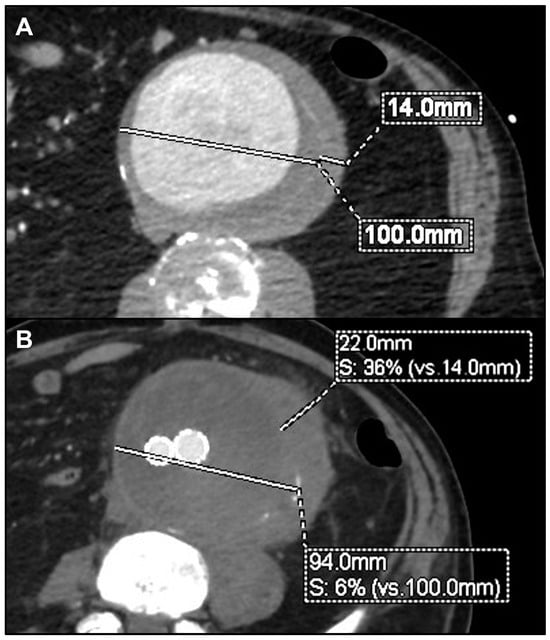

| 1 | M | 85 | Endocarditis | Staphylococcus aureus | Yes | Symptomatic rapidly growing thoracic PAU | Oxacyllin | TEVAR | Alive | 48 | Proximal disease progression | Redo TEVAR ± LSA embolization |

| 5 | M | 68 | Sepsis in porcelain aorta | Salmonella spp. Non-Typhi | Yes | Contained ruptured infrarenal atheromatous plaque | Ampicillin ± Sulbactam | EVAR (tube graft) | Alive | 57 | Proximal and distal disease progression | Bifurcated EVAR |